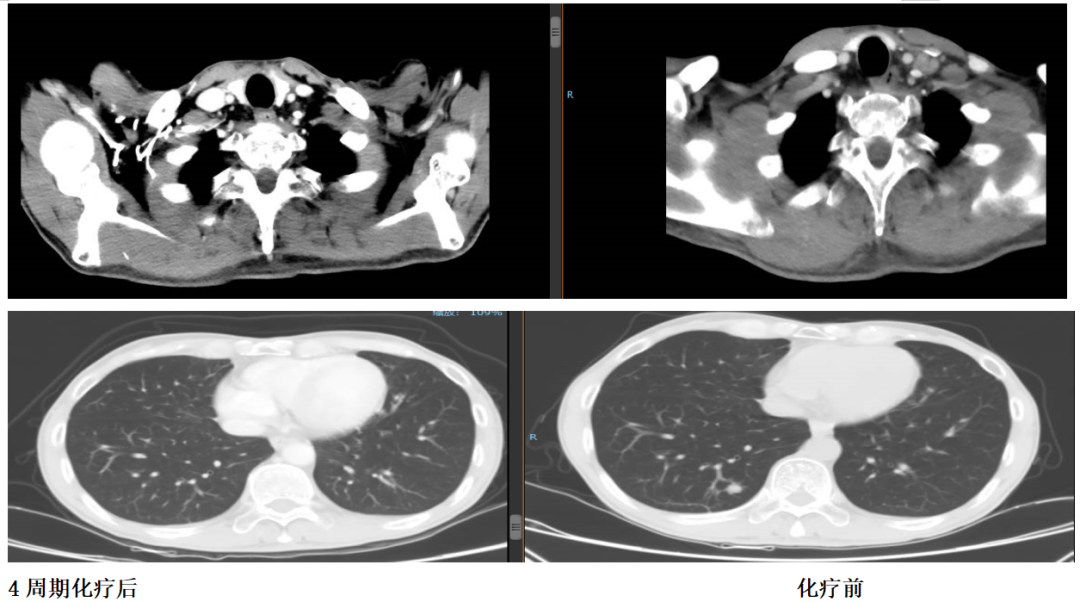

2018年10月23日至2019年2月3日行顺铂+氟尿嘧啶联合赫赛汀方案治疗5周期,疗效评估PR。

2019年1月24日,经4个周期赫赛汀+DF后,患者肝脏转移灶明显缩小。

患者化疗后出现3度胃肠道反应,3度骨髓抑制。第5周期化疗后出现感染性休克,遂停止联合化疗。